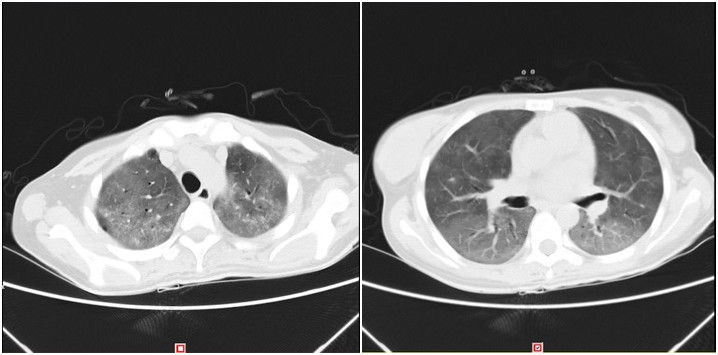

28岁的刘女士在外院诊断为非霍奇金淋巴瘤,弥漫性大B细胞型,化疗8次后,出现气促、活动明显受限,渐至张口呼吸,说话不能成句,呼吸极度困难,被紧急送入住捷克论坛 呼吸与危重症医学科(RICU),入院时休克血压,高浓度吸氧下血氧饱和度75--80%,CT示“双肺弥漫性病变”,“白肺”,诊断考虑:重症肺炎、ARDS、感染性休克。